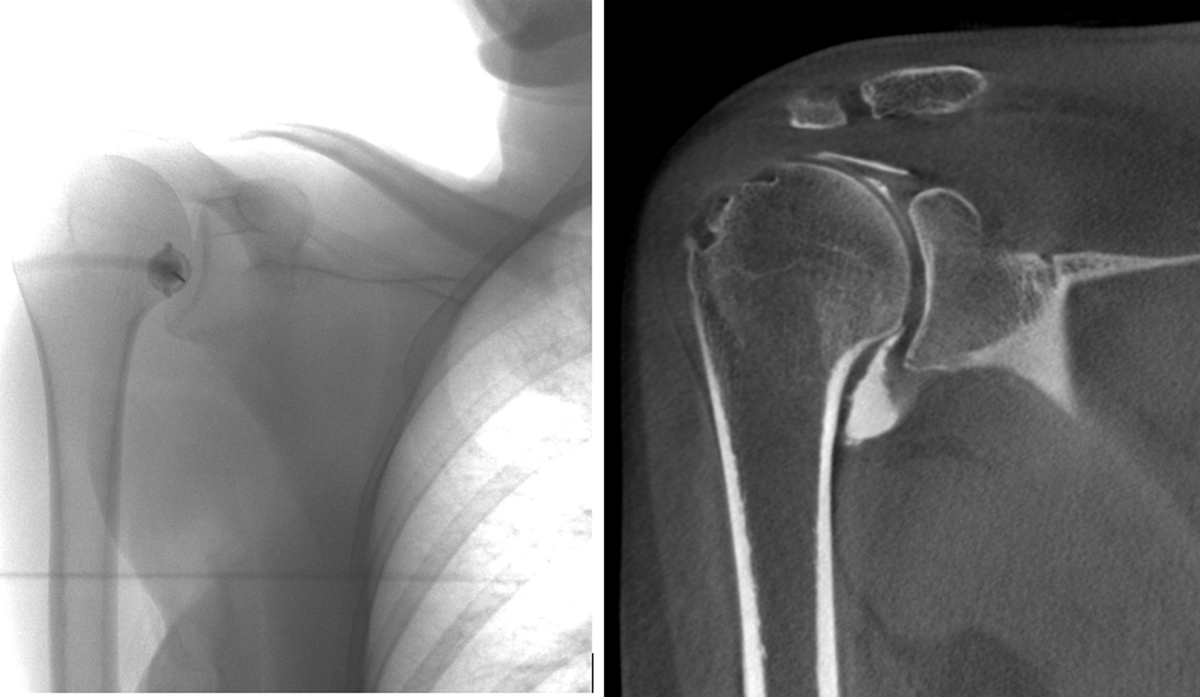

With this larger gantry and higher tube voltage (120 kV), large joints and body parts can be examined. The high-spatial resolution of bony architecture leads to a very good evaluation of fusion material in cervical and lumbar spine (Figure 1). High-spatial resolution images of cartilage surface after intra-articular contrast injection, already shown very useful in other joints such as the wrist [78], can now be obtained in the shoulder joint (Figure 2). The availability of fluoroscopy makes it possible to perform the contrast injection while the patient is installed for the scan, keeping the time between injection and scan to a minimum.

Figure 2